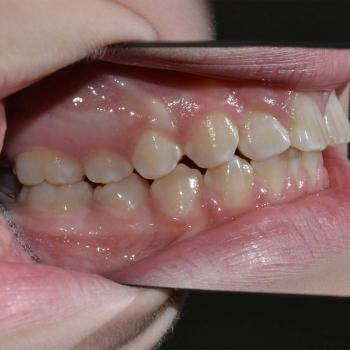

Gergő és édesanyja fogorvosi javaslatra keresett fel, a bal felső 2. kisőrlő hibás pozíciója miatt. A konzultáció során egyértelművé vált, hogy az előbb említett fog helyét teljes mértékben elfoglalták az előtte, illetve mögötte elhelyezkedő fogak, gyakorlatilag 0mm helyet hagyva a probléma megoldására. Ilyen esetekben felmerül a szájpadi irányba kiszorult fog eltávolítása, de a felső fogívben tapasztalható résesség a helyteremtés mellett szólt.

A kezelés első lépéseként Frog készülékkel hátrafelé mozdítottuk a bal felső első nagyőrlőt, ezzel elrendezve a nagyőrlők érintkezését, másfelől 4mm helyet teremtve a második kisőrlő számára. Ez a hely még nem volt elegendő, így rögzített fogszabályozóval zártuk a nagymetszők közötti, illetve az első kisőrlő előtti rést, mellyel további 2.5mm helyet nyertünk. Az így már 6.5mm-es rés elegendő volt ahhoz, hogy a kiszorult kisőrlőt bemozdítsuk a kívánt pozícióba, ezzel kialakítva egy funkcionálisan megfelelő és esztétikus felső fogívet. Mivel a harapás korrekciója, azaz a funkció helyreállítása kizárólag a felső fogív kezelésével is kivitelezhető volt, így a szülők nem kérték az alsó fogív torlódásának a megoldását.